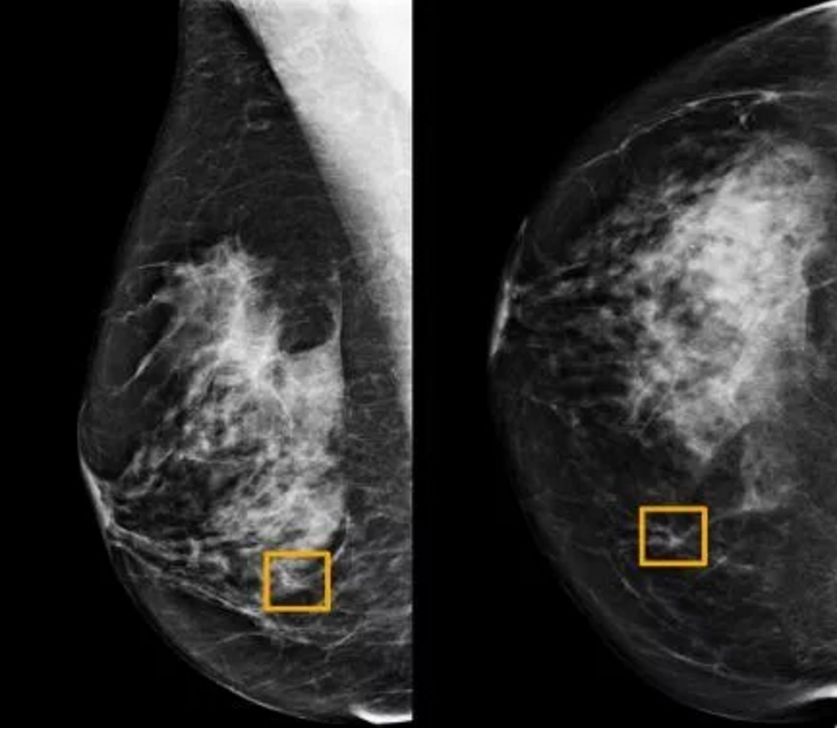

乳腺癌检测AI模型

人工智能系统在医学诊断中又有了新的应用。

在发表于《自然》( Nature )的最新研究中,谷歌健康团队开发了一种能够检测乳腺癌的AI系统。

目前,人类专家在解读乳房X光图像时,准确率仍有上升空间。

而这款深度学习AI模型可以通过筛查乳房X光图像来检测乳腺癌。研究人员利用两个大型数据集对该系统进行了测评。结果显示:出现假阳性与假阴性的概率都下降了,其表现优于另一项研究中的放射科专家。

此外,该系统协助放射科专家工作时,可大幅减少人类专家的工作量。

Screening mammography aims to identify breast cancer at earlier stages of the disease, when treatment can be more successful1. Despite the existence of screening programmes worldwide, the interpretation of mammograms is affected by high rates of false positives and false negatives2. Here we present an artificial intelligence (AI) system that is capable of surpassing human experts in breast cancer prediction. To assess its performance in the clinical setting, we curated a large representative dataset from the UK and a large enriched dataset from the USA. We show an absolute reduction of 5.7% and 1.2% (USA and UK) in false positives and 9.4% and 2.7% in false negatives. We provide evidence of the ability of the system to generalize from the UK to the USA. In an independent study of six radiologists, the AI system outperformed all of the human readers: the area under the receiver operating characteristic curve (AUC-ROC) for the AI system was greater than the AUC-ROC for the average radiologist by an absolute margin of 11.5%. We ran a simulation in which the AI system participated in the double-reading process that is used in the UK, and found that the AI system maintained non-inferior performance and reduced the workload of the second reader by 88%. This robust assessment of the AI system paves the way for clinical trials to improve the accuracy and efficiency of breast cancer screening.